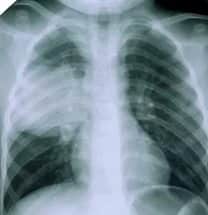

Легочный эхинококкоз на стадии появления клинических симптомов проявляется довольно ярко (см. фото пораженного легкого ниже). У пациентов наблюдаются:

- выраженная аллергическая реакция (интоксикационный синдром);

- высокая температура;

- болевые ощущения в области легких;

- кашель с примесью крови.

Разрыв кистозного образования может привести к развитию пневмонии или ателектаза. Эхинококкоз у пациентов с прорывом паразитарной кисты в перикард или плевру может вызвать анафилактический шок или тампонаду сердца, что в свою очередь может привести к летальному исходу.

В легких эхинококк гранулезус, как правило, выявляется раньше, чем в других органах. Это связано с тем, что наличие микроорганизмов и кист в легочной ткани вызывает у человека затруднения с дыханием.

Также осуществляется аппаратная диагностика, которая может включать рентгенографию, магнитно-резонансную томографию (МРТ), компьютерную томографию, ультразвуковое исследование (УЗИ), лапароскопию и другие методы. В зависимости от того, какой орган затронут по предварительному диагнозу, могут быть назначены дополнительные обследования.